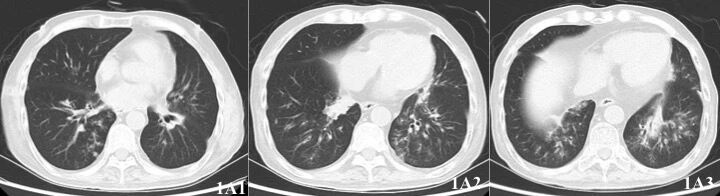

术后第67天(2018-5-10),患者出现夜间呼吸困难,需持续无创呼吸机辅助,伴咳嗽、咳白粘痰,粘稠不易咳出,伴双下肢水肿。血常规:WBC 3.16*109/L, NE 2.15*109/L,LY 0.78*109/L;CD4+ T细胞 244 个/µl;PCT 0.26ng/ml;FK506 10.9ng/ml;BNP 152.67ng/ml。胸部低剂量CT可见双肺下叶新发结节影(图1A1-3)。

图1A1-3. 2018-5-18胸部低剂量CT:双下肺新发结节、斑片影

2018年7月20日,抗真菌治疗49天后,停用米卡芬净。2018年8月30日复查CT(图1B1-3)及气管镜(图2B1-2)基本正常。后多次复查BALF病原学无帚霉证据。患者于2018年9月5日停用特比萘芬及伯沙康唑,共计118天。目前患者术后近4年,规律随访中。

图1B1-3. 2018-8-30复查胸部低剂量CT:双下肺结节及斑片影基本吸收。